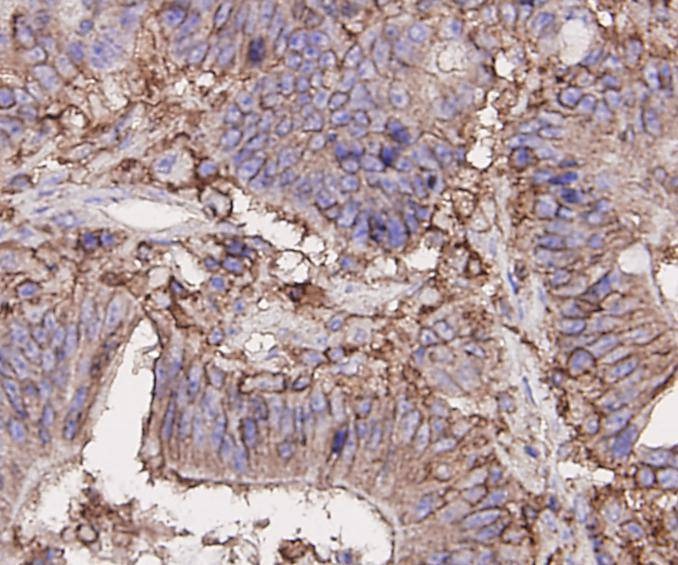

3. Immunohistochemical analysis of paraffin-embedded human colon carcinoma tissue using anti-CD44 antibody. Counter stained with hematoxylin.